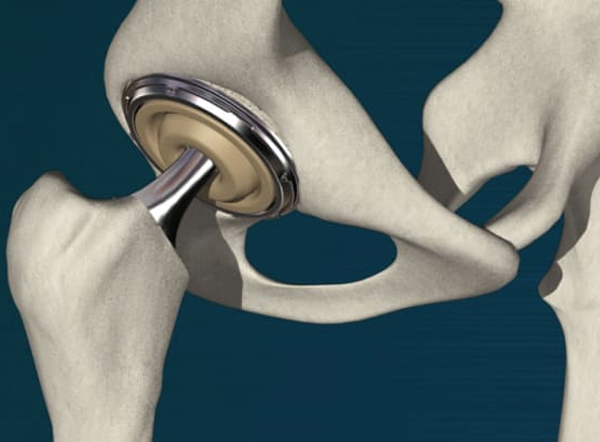

• ロボティックアームを用いてインプラントを設置します。

• 大腿骨にインプラントを設置します。

• 各インプラント部品を設置します。

• 人工股関節の設置が完了しました。